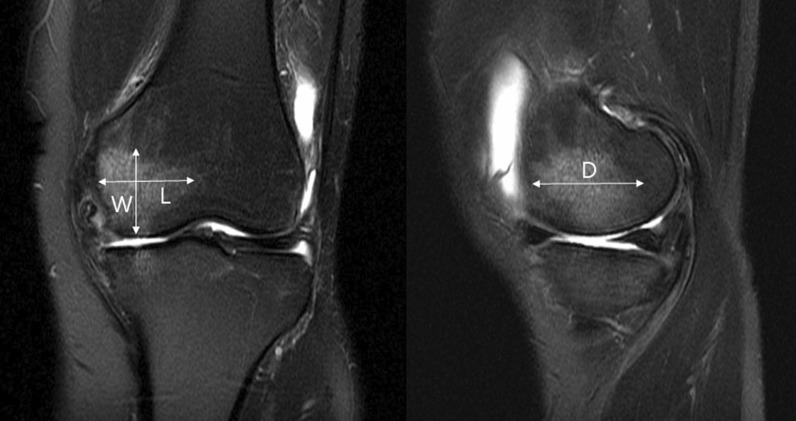

Methods: A total of 138 patients who underwent medial open-wedge HTO using locking plate were included in this study. BME was observed in 108 patients using preoperative magnetic resonance imaging. Clinical results were evaluated before HTO and postoperatively at 12 months. Moreover, we evaluated the factors affecting the clinical results.

Abstract Image